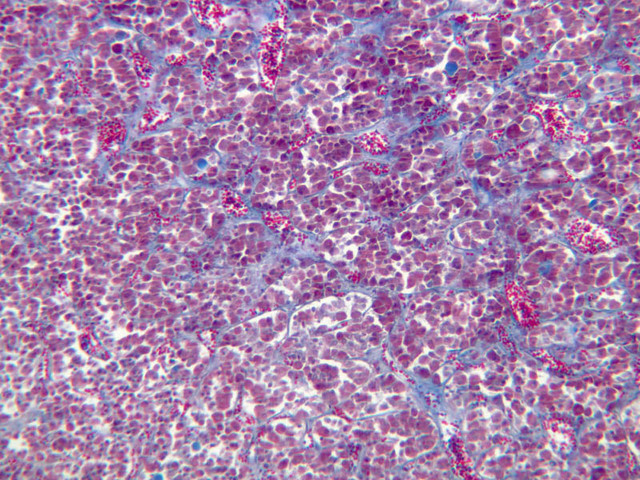

The neurohypophysis arises as an outpocketing of neuroectoderm from the floor of a portion of the brain called diencephalon. It is divisible into the pars nervosa, which forms the posterior portion of the main mass of the pituitary, and the infundibulum, or pituitary stalk. In H&E-stained sections, the neurohypophysis is distinctly eosinophilic. The adenohypophysis (anterior pituitary) has three different types of secretory cells, which are best visualized in the trichrome-stained preparation on slide B-65: (1) acidophils have a reddish staining cytoplasm, owing to the presence of secretory granules. These cells secrete growth hormone (GH) and prolactin (PRL); (2) basophils are slightly larger cells with bluish staining granules present in the cytoplasm. These cells tend to occur in small groups or clusters. Basophils are responsible for the production of thyroid stimulating hormone (TSH), adrenocorticotrophic hormone (ACTH), and the gonadotrophic hormones follicle stimulating hormone (FSH) and luteinizing hormone (LH ); (3) chromophobes or C cells are smaller cells and have only a small amount of poorly staining cytoplasm (B-63, H&E [2.5x-labeled, 10x, 20x, 40x-labeled] [2.5x, 10x, 20x, 40x-labeled]; B-65, trichrome [2.5x, 10x, 20x, 40x-labeled] [2.5x, 10x, 20x, 40x] [10x, 20x, 40x-labeled] [2.5x, 10x, 20x, 40x] [2.5x, 10x, 20x, 40x]). What is the target organ of each of the hormones produced by the adenohypophysis? Note the rich vascularity of the adenohypophysis. Can you describe the blood supply and its significance?

The adrenal gland (slide B-59, H&E [2.5x-labeled, 10x-labeled, 20x, 40x-labeled] [2.5x, 10x-labeled, 20x, 40x]; B-60, H&E [2.5x-labeled, 10x, 20x, 40x]; B-62, H&E [10x, 20x, 40x] [2.5x, 10x]) is a composite organ consisting of two functionally, structurally and embryologically different parts—an outer cortex and an inner medulla. Observe the gland at low power. Find the loosely organized tissue that comprises the medulla and the partially-separated columns of cells that make up the cortex. Scan the capsule and the tissue around it, looking for nerves and blood vessels. Study the pattern of cortical vasculature. In a pattern similar to that seen in the pars distalis of the pituitary, sinusoids run along the edges of columns or cords of cells. Owing to different arrangements of its constituent cells, the adrenal cortex has a layered appearance. From the capsule inward, these cortical layers are known as the zona glomerulosa, the zona fasciculata, and the zona reticularis.

The zona glomerulosa is located immediately beneath the capsule (B-60 adrenal gland, dog [10x, 20x] [20x, 40x]; B-59 [2.5x, 10x, 20x] [2.5x, 10x, 20x]). Its constituent cells are arranged in arcs or spheres, and, owing to their relatively small size, their nuclei appear to be close together. Cells of the zona glomerulosa secrete mineralocorticoids (e.g., aldosterone). The zona fasciculata consists of parallel columns or cords of cells that radiate toward the medulla and are separated by blood sinusoids (B-60 [2.5x, 10x, 20x, 40x]; B-62 [20x, 40x]). Owing to the extraction of lipids during histological processing, the cytoplasm of cells in the zona fasciculata appears highly vacuolated or "foamy". Cells of the zona fasciculata secrete glucocorticoids (e.g., hydrocortisone & cortisone) and some gonadocorticoids (weak androgens). The zona reticularis is the deepest cortical layer and lies adjacent to the medulla (B-60 [20x, 40x]; B-62 [20x, 40x]). It is characterized by irregular, interconnecting cords of cells which are separated by anastomosing capillary networks or sinusoids. Cells of the zona reticularis, which are smaller than those of zona fasciculata and do not contain as many lipid vacuoles, secrete gonadocorticoids and some glucocorticoids.